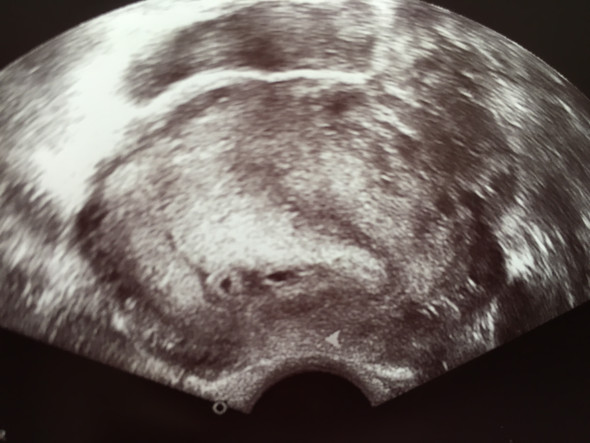

Frühe Zwillingsschwangerschaften im Ultraschall Eineiige Zwillinge in der 55 Schwangerschaftswoche Schwangerschaften entstehen – und das ist nun wirklich nicht überraschend neu – nachdem eine Eizelle von einem Samenfaden befruchtet wurde Zwillinge können auf zwei Arten entstehen. Ultraschall 5 SSW Rechts im Bild ist die Fruchthöhle (schwarz) zu sehen Der Embryo ist jetzt etwa zwei Millimeter lang und auf dem Ultraschall zu dieser Zeit oft noch nicht zu erkennen Trotzdem beginnt in dieser Woche das Herz des Embryos zu schlagen. Sie sind in SSW 4 (SSW 4 06) oder in der 5 Schwangerschaftswoche Jetzt können Sie einen Schwangerschaftstest machen!.

5 SSW Ultraschall Das ist zu sehen Schwarzsehen war noch nie so schön Auf dem Ultraschall bestätigt in der 5 SSW ein kleiner schwarzer Punkt, dass Sie schwanger sind – das ist die Fruchtwasserhöhle, die jetzt circa einen Zentimeter groß ist Der Ultraschall bedingt, dass sie sich als schwarze Blase auf dem Bild abzeichnet. 2 » »» Sonnenschirm 373 Beiträge 1015. Das Baby in der 6 SSW Der Embryo ist etwa 4mm groß und wiegt weniger als 1 g Seine Form ist leicht gebeugt und weist einen erkennbaren Ansatz einer Taille auf Das Herz hat bisher nur eine Herzkammer – langsam entwickelt sich jedoch die Scheidewand, die das Herz in die rechte und die linke Herzkammer unterteilt Es schlägt unregelmäßig.

Was in der 5 SSW auf dem Ultraschall zu erkennen ist Auf dem Ultraschall bestätigt in der 5 SSW ein kleiner schwarzer Punkt, dass Du schwanger bist Das ist die Fruchtwasserhöhle, die jetzt circa 1 cm groß ist Der Embryo selbst ist noch nicht zu erkennen – er ist noch viel zu klein Etwa ab der 7. 5 SSW Ultraschall Das ist zu sehen Schwarzsehen war noch nie so schön Auf dem Ultraschall bestätigt in der 5 SSW ein kleiner schwarzer Punkt, dass Sie schwanger sind – das ist die Fruchtwasserhöhle, die jetzt circa einen Zentimeter groß ist Der Ultraschall bedingt, dass sie sich als schwarze Blase auf dem Bild abzeichnet. Zu den sichersten Anzeichen, dass Du Zwillinge erwartest, gehören zwei Herzschläge im Ultraschall In der Regel werden Zwillinge bereits bei der ersten Ultraschalluntersuchung entdeckt, die etwa in der sechsten Schwangerschaftswoche erfolgt ;.